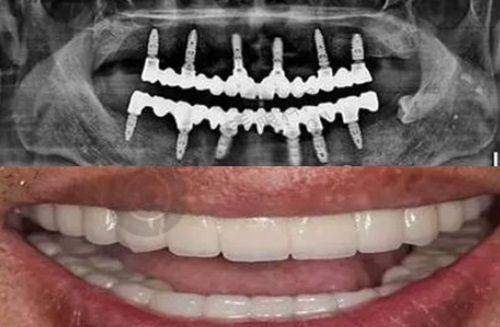

项目一条龙服务:这里开展的项目众多,不管你是牙齿种植、矫正,还是修复、治疗等问题,都能在这里得到解决,真正实现了一条龙服务,大部分牙齿问题都能在这搞定。

种牙 | 国产康盛种植牙 | 5750元起/颗 |

半口种植牙 | 6.4万元起 | |

全口种植牙 | 12.8万元起 | |